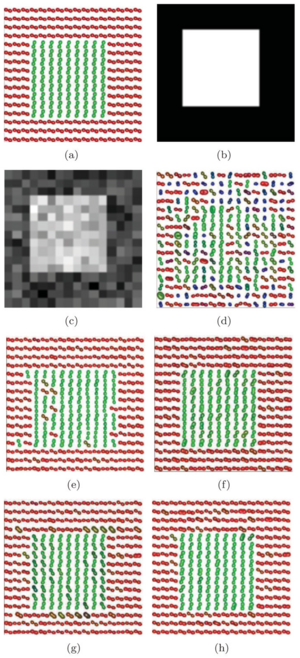

Seeing More by Showing Less: Orientation-Dependent Transparency Rendering for Fiber Tractography Visualization

Publication: PLoS One. 2015 Oct 7;10(10):e0139434. PMID: 26444010 | PDF Authors: Tax CM, Chamberland M, van Stralen M, Viergever MA, Whittingstall K, Fortin D, Descoteaux M, Leemans A. Institution: Image Sciences Institute, University Medical Center Utrecht, Utrecht, The Netherlands. Background/Purpose: Fiber tractography plays an important role in exploring the architectural organization of fiber trajectories, both in fundamental neuroscience and in clinical applications. With the advent of diffusion MRI (dMRI) approaches that can also model "crossing fibers", the complexity of the fiber network as reconstructed with tractography has increased tremendously. Many pathways interdigitate and overlap, which hampers an unequivocal 3D visualization of the network and impedes an efficient study of its organization. We propose a novel fiber tractography visualization approach that interactively and selectively adapts the transparency rendering of fiber trajectories as a function of their orientation to enhance the visibility of the spatial context. More specifically, pathways that are oriented (locally or globally) along a user-specified opacity axis can be made more transparent or opaque. This substantially improves the 3D visualization of the fiber network and the exploration of tissue configurations that would otherwise be largely covered by other pathways. We present examples of fiber bundle extraction and neurosurgical planning cases where the added benefit of our new visualization scheme is demonstrated over conventional fiber visualization approaches. Funding:

|